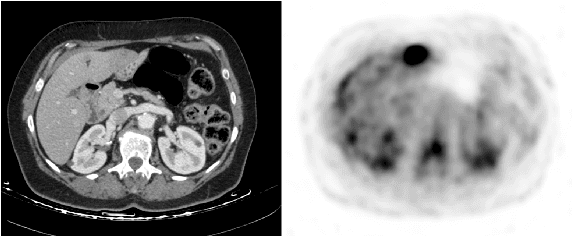

Abstract:In this work we present a novel system for generation of virtual PET images using CT scans. We combine a fully convolutional network (FCN) with a conditional generative adversarial network (GAN) to generate simulated PET data from given input CT data. The synthesized PET can be used for false-positive reduction in lesion detection solutions. Clinically, such solutions may enable lesion detection and drug treatment evaluation in a CT-only environment, thus reducing the need for the more expensive and radioactive PET/CT scan. Our dataset includes 60 PET/CT scans from Sheba Medical center. We used 23 scans for training and 37 for testing. Different schemes to achieve the synthesized output were qualitatively compared. Quantitative evaluation was conducted using an existing lesion detection software, combining the synthesized PET as a false positive reduction layer for the detection of malignant lesions in the liver. Current results look promising showing a 28% reduction in the average false positive per case from 2.9 to 2.1. The suggested solution is comprehensive and can be expanded to additional body organs, and different modalities.

Abstract:In this work we present a novel system for PET estimation using CT scans. We explore the use of fully convolutional networks (FCN) and conditional generative adversarial networks (GAN) to export PET data from CT data. Our dataset includes 25 pairs of PET and CT scans where 17 were used for training and 8 for testing. The system was tested for detection of malignant tumors in the liver region. Initial results look promising showing high detection performance with a TPR of 92.3% and FPR of 0.25 per case. Future work entails expansion of the current system to the entire body using a much larger dataset. Such a system can be used for tumor detection and drug treatment evaluation in a CT-only environment instead of the expansive and radioactive PET-CT scan.